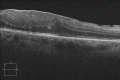

The aim of this article was to report our findings in a case of infectious uveitis in which the DNAs of both Toxoplasma gondii and human herpesvirus 7 (HHV-7) were detected in the vitreous fluid. A 31-year-old Brazilian man was examined in our hospital with a one-month history of blurred vision (20/40) in the right eye. He had been diagnosed with ocular toxoplasmosis of the right eye at nine years of age and has had repeated relapses. Because of the persistent vitreous opacities and refractoriness to acetylspiramycin and betamethasone, pars plana vitrectomy was performed. Multiplex PCR of the vitreous sample demonstrated the DNAs for both T. gondii and HHV-7. Trimethoprim/sulfamethoxazole with prednisone was prescribed. Six months after the beginning of the therapy, a resolution of the retinochoroiditis was found and the vision recovered to 20/25. Two months later, we performed a pars plana vitrectomy for an epiretinal membrane. The DNAs of both T. gondii and HHV-7 were not detected in the vitreous fluid and the epiretinal membrane. After continued treatment, the best-corrected visual acuity (BCVA) in the right eye improved to 20/16 and the metamorphopsia was reduced. It is inferred from this work that HHV-7 reactivation can activate refractory infectious uveitis in patients with chronic ocular toxoplasmosis.